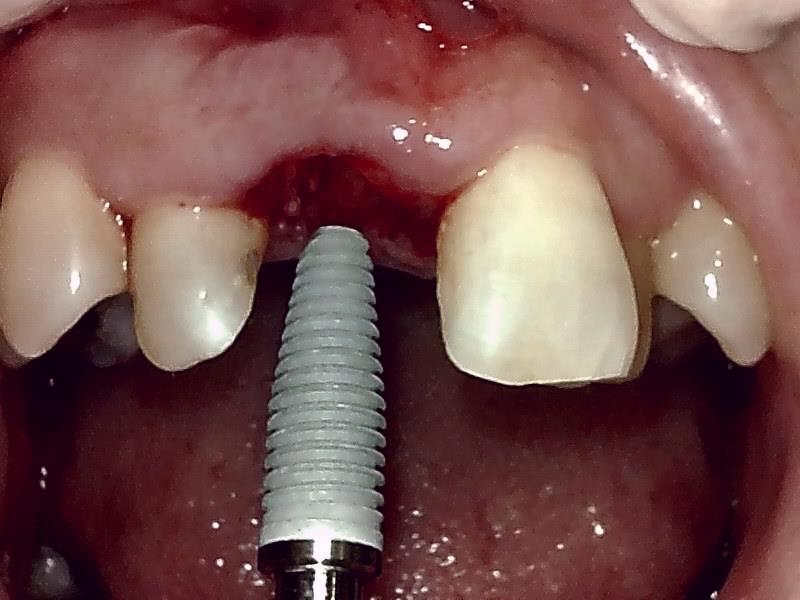

インプラント体の埋入